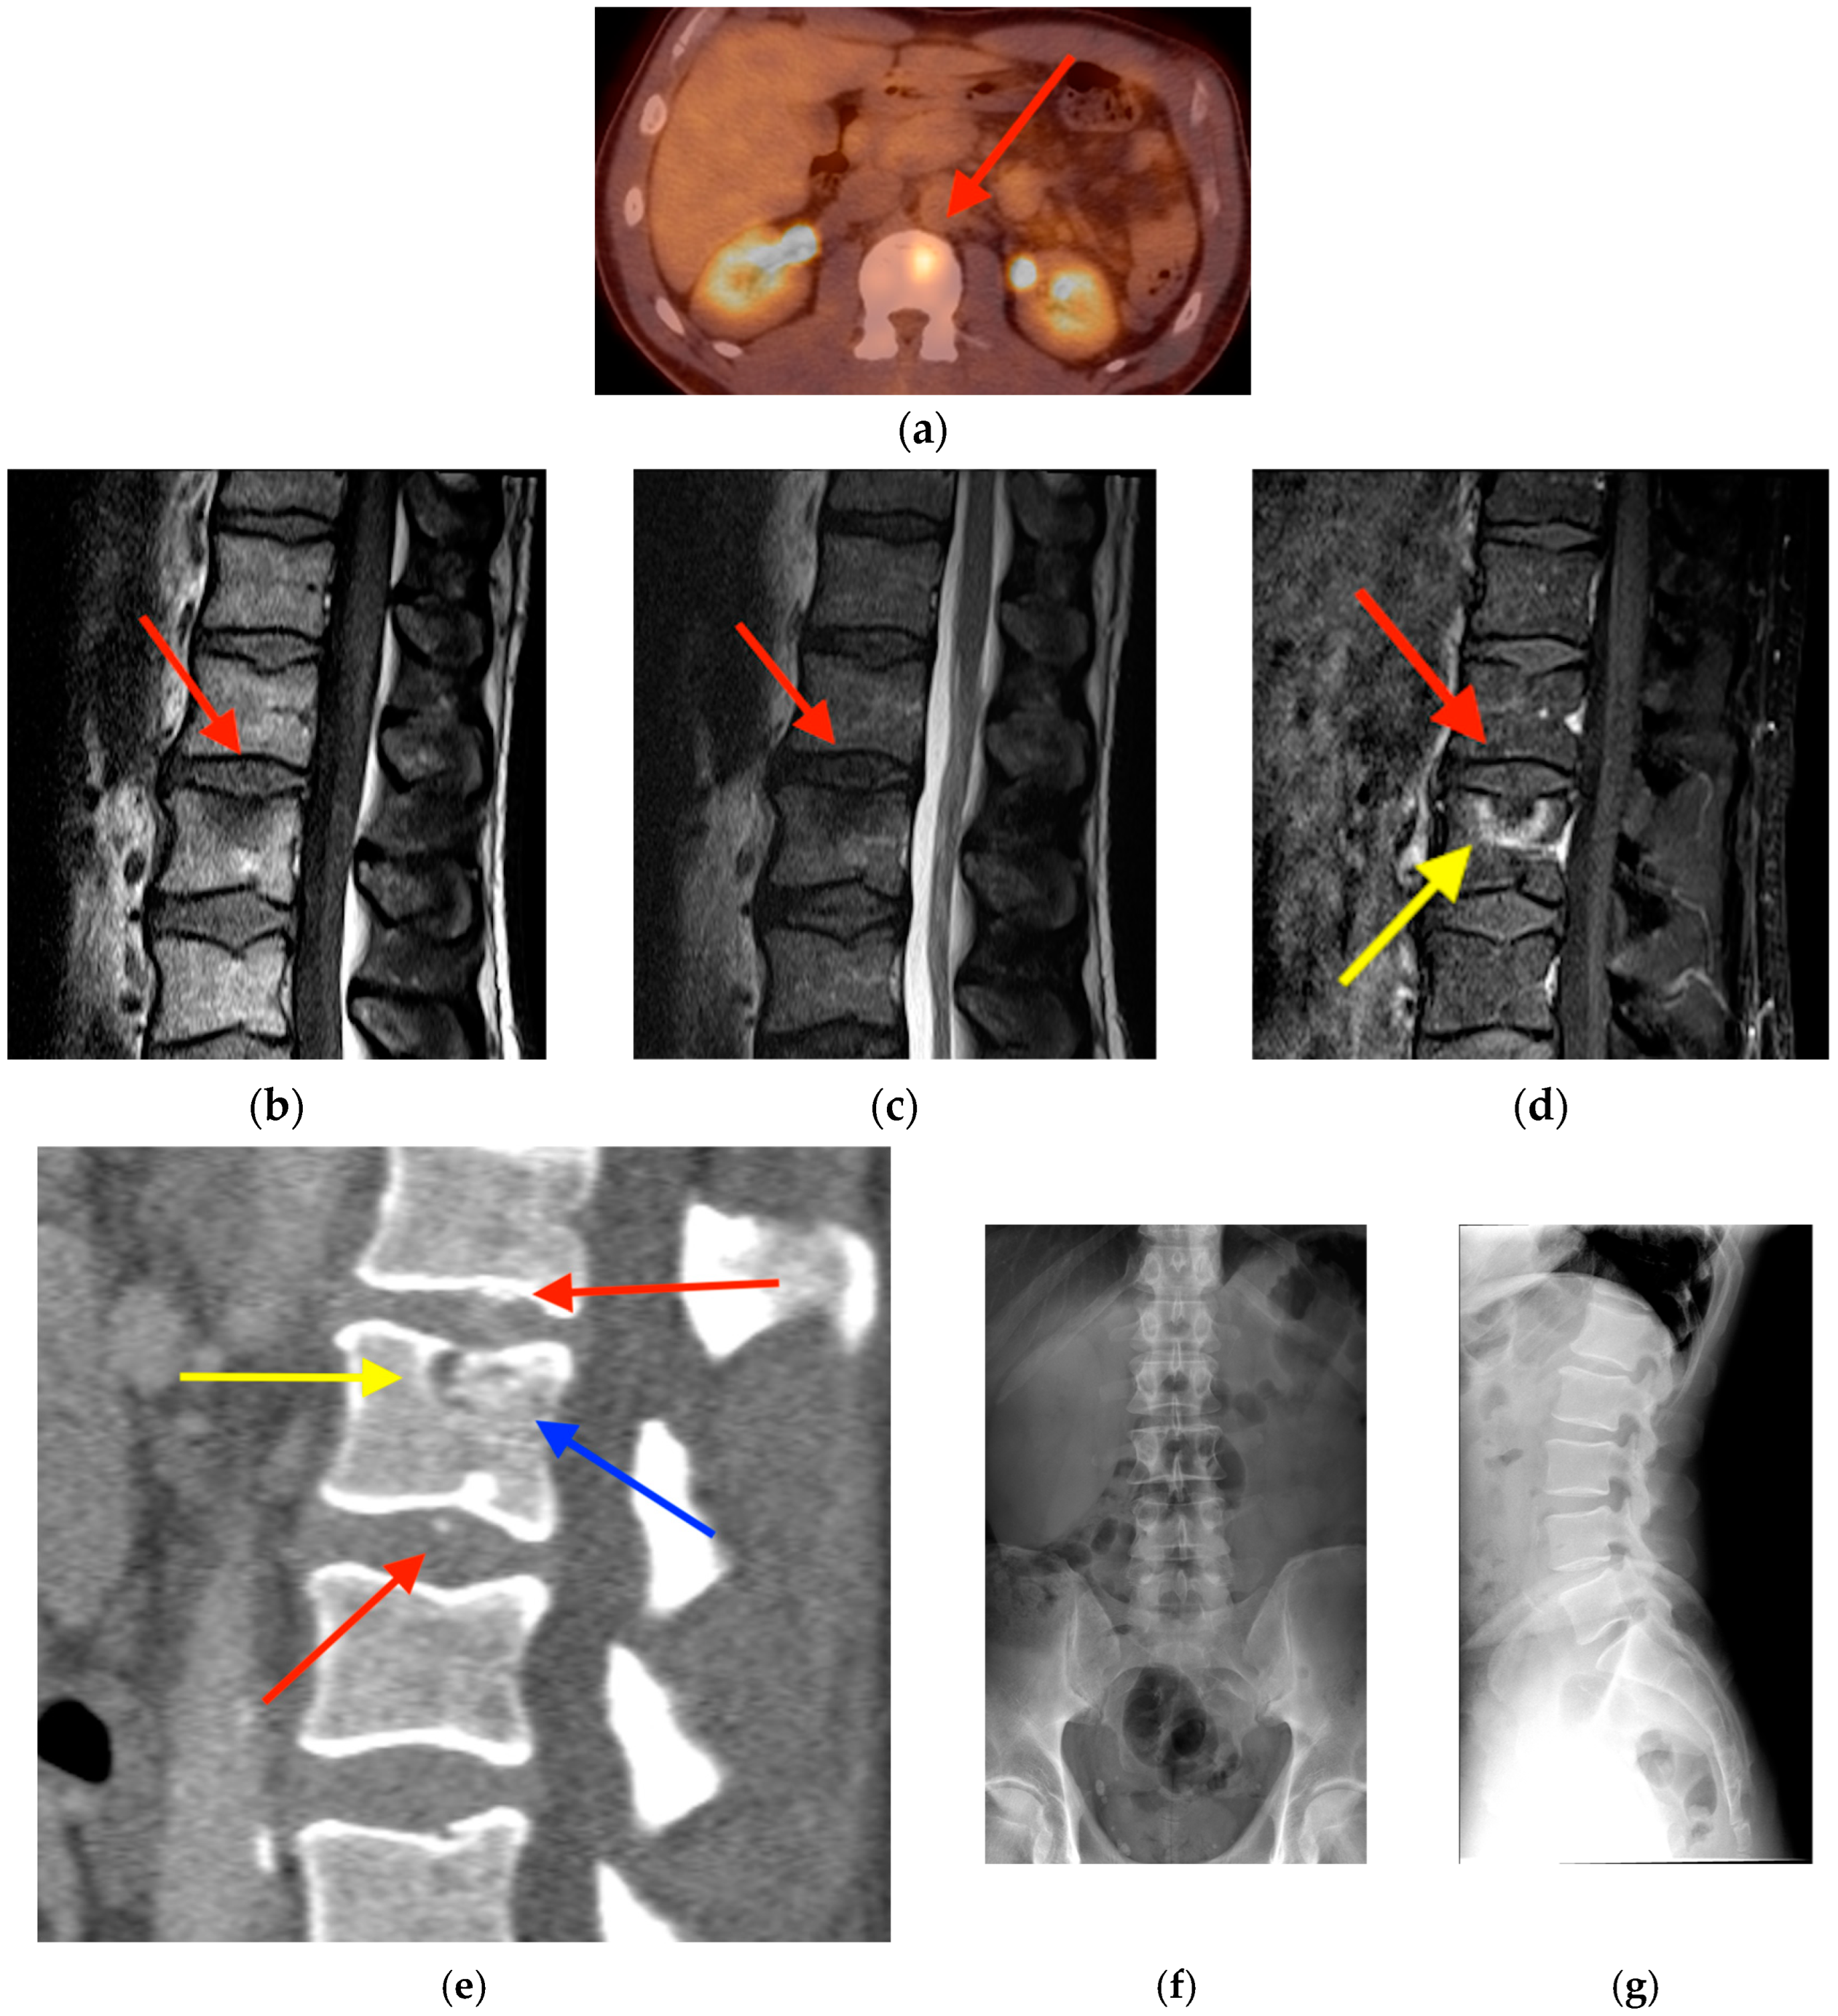

2.1. Fracture

- Oh, D.; Huh, S.J. Insufficiency fracture after radiation therapy. Radiat. Oncol. J. 2014, 32, 213–220. [Google Scholar] [CrossRef]

- Chung, Y.K.; Lee, Y.K.; Yoon, B.H.; Suh, D.H.; Koo, K.H. Pelvic Insufficiency Fractures in Cervical Cancer After Radiation Therapy: A Meta-Analysis and Review. In Vivo 2021, 35, 1109–1115. [Google Scholar] [CrossRef]

- Blomlie, V.; Rofstad, E.K.; Talle, K.; Sundfør, K.; Winderen, M.; Lien, H.H. Incidence of radiation-induced insufficiency fractures of the female pelvis: Evaluation with MR imaging. AJR Am. J. Roentgenol. 1996, 167, 1205–1210. [Google Scholar] [CrossRef]

- Abe, H.; Nakamura, M.; Takahashi, S.; Maruoka, S.; Ogawa, Y.; Sakamoto, K. Radiation-induced insufficiency fractures of the pelvis: Evaluation with 99mTc-methylene diphosphonate scintigraphy. AJR Am. J. Roentgenol. 1992, 158, 599–602. [Google Scholar] [CrossRef]

- Salavati, A.; Shah, V.; Wang, Z.J.; Yeh, B.M.; Costouros, N.G.; Coakley, F.V. F-18 FDG PET/CT findings in postradiation pelvic insufficiency fracture. Clin. Imaging 2011, 35, 139–142. [Google Scholar] [CrossRef]

- Kato, K.; Aoki, J.; Endo, K. Utility of FDG-PET in differential diagnosis of benign and malignant fractures in acute to subacute phase. Ann. Nucl. Med. 2003, 17, 41–46. [Google Scholar] [CrossRef] [PubMed]

- Shin, D.S.; Shon, O.J.; Byun, S.J.; Choi, J.H.; Chun, K.A.; Cho, I.H. Differentiation between malignant and benign pathologic fractures with F-18-fluoro-2-deoxy-D-glucose positron emission tomography/computed tomography. Skelet. Radiol. 2008, 37, 415–421. [Google Scholar] [CrossRef]

- Zhong, X.; Zhang, L.; Dong, T.; Mai, H.; Lu, B.; Huang, L.; Li, J. Clinical and MRI features of sacral insufficiency fractures after radiotherapy in patients with cervical cancer. BMC Womens Health 2022, 22, 166. [Google Scholar] [CrossRef]